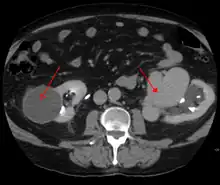

AVMs are diagnosed primarily by the following imaging methods:[12]

- Computerized tomography (CT) scan is a noninvasive X-ray to view the anatomical structures within the brain to detect blood in or around the brain. A newer technology called CT angiography involves the injection of contrast into the blood stream to view the arteries of the brain. This type of test provides the best pictures of blood vessels through angiography and soft tissues through CT.

- Magnetic resonance imaging (MRI) scan is a noninvasive test, which uses a magnetic field and radio-frequency waves to give a detailed view of the soft tissues of the brain.

- Magnetic resonance angiography (MRA) – scans created using magnetic resonance imaging to specifically image the blood vessels and structures of the brain. A magnetic resonance angiogram can be an invasive procedure, involving the introduction of contrast dyes (e.g., gadolinium MR contrast agents) into the vasculature (circulatory system) of a patient using a catheter inserted into an artery and passed through the blood vessels to the brain. Once the catheter is in place, the contrast dye is injected into the bloodstream and the MR images are taken. Additionally or alternatively, flow-dependent or other contrast-free magnetic resonance imaging techniques can be used to determine the location and other properties of the vasculature.

AVMs can occur in various parts of the body: